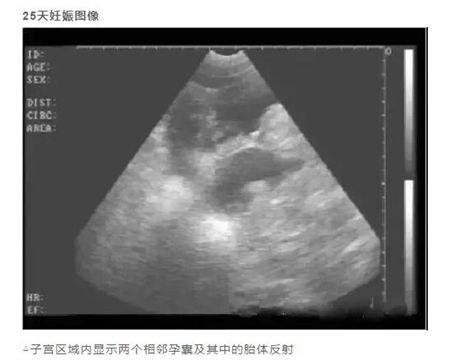

20天孕期左右的母猪,即可进行B超测孕,但由于羊水太少,图像不好判断,准确度也会因检测人员经验因素有所影响,容易造成误判,而且检查时间长,耗费人力。